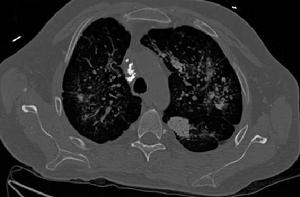

早期出現肺泡炎,肺泡內有漿液和細胞成分,肺間質內有大量單核細胞,部分淋巴細胞,漿細胞,肺泡巨噬細胞等炎性細胞浸潤,肺泡結構完整。進入晚期,慢性炎症已減輕,肺泡結構為堅實的膠原代替,肺泡壁被破壞,形成擴張的蜂窩肺。膠原、細胞外基質、成纖維細胞分布在間質中,肺泡上皮化生為鱗狀上皮。基於以上病理變化,臨床上多表現為進行性呼吸困難或伴有刺激性乾咳,胸部X線顯示兩中下肺野網狀陰影,肺功能為限制性通氣功能障礙。病情呈持續性進展,最終因呼吸衰竭而死亡。

肺纖維灶,常為肺部感染後,自然癒合後遺留的纖維化病灶。肺間質組織由膠原蛋白、彈性素及蛋白醣類構成,當纖維母細胞受到化學性或物理性傷害時,會分泌膠原蛋白進行肺間質組織的修補,進而造成肺臟纖維化;即肺臟受到傷害後,人體修復產生的結果。 常見的原因是肺結核已經痊癒或其它的損傷後修復的表現。如果纖維化範圍小,對身體基本不影響,如果範圍廣,就可能導致肺功能降低,出現缺氧和呼吸困難等。 正常肺間質由少量的間質巨噬細胞,成纖維細胞,肌成纖維細胞以及肺基質,膠原,大分子物質,非膠原蛋白等組成。當肺間質發生病變時,上述成分的數量和性質都會發生改變。表現為明顯的炎症侵犯肺泡壁和鄰近的肺泡壁腔,Ⅱ型肺泡上皮細胞替代Ⅰ型肺泡上皮細胞,肺泡間隔明顯增厚以及肺纖維化,最後肺毛細血管喪失。